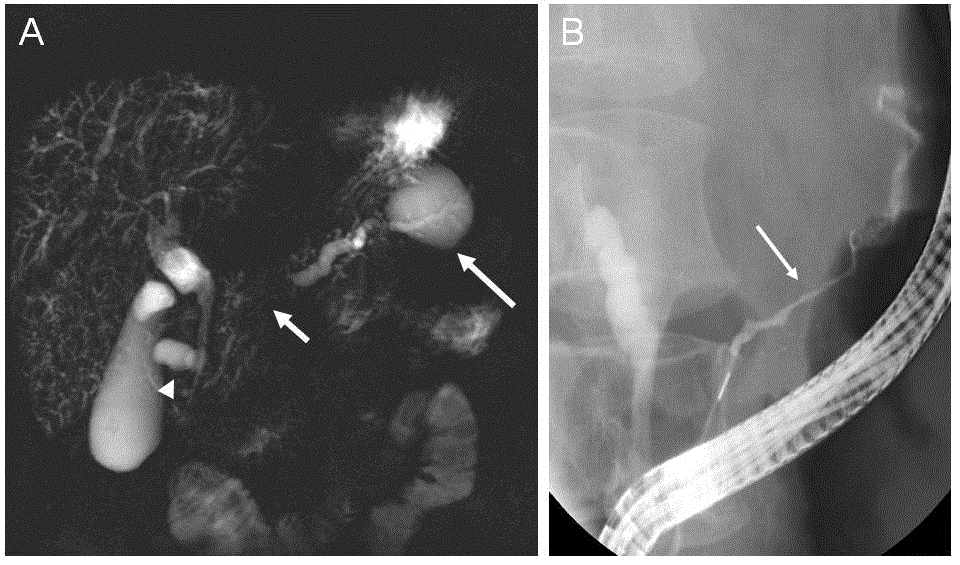

Figure 3. Secretin-enhanced magnetic resonance cholangiopancreatography (s-S-MRCP) and endoscopic retrograde cholangiopancreatography (ERCP) studies. (A) Secretinenhanced S-MRCP showed main pancreatic duct stenosis (short arrow) with upstream dilatation and a pseudocyst in the tail of the pancreas (long arrow). Another pseudocyst was observed in the duodenal groove adjacent to the common bile duct (arrowhead).   Intrahepatic bile ducts were of irregular caliber and presented multiple strictures, featuring sclerosing cholangitis. (B) ERCP showed a long and incomplete stricture involving the main pancreatic duct (arrow).

In our case, s-MRCP and ERCP showed stenosis of the main pancreatic duct with upstream dilatation and 2 pseudocysts, very unusual in AIP type 1, associated with sclerosing cholangitis. Indeed, a long stricture (1/3 the length of the main pancreatic duct) and lack of upstream dilatation from the stricture (< 5mm) has been proposed as a key features of AIP on ERCP [19]. Consensus diagnostic protocols of imaging in the diagnosis and management of AIP includes contrast-enhanced CT and MRI for pancreatic parenchymal lesion localization and characterization, ERCP and S-MRCP to assess pancreatic duct involvement. However, 18FDG-PET/CT imaging has a valuable role in assessing the involvement of extra-pancreatic sites, staging extent and activity of disease, guiding organ biopsy, and monitoring response to treatment [20].